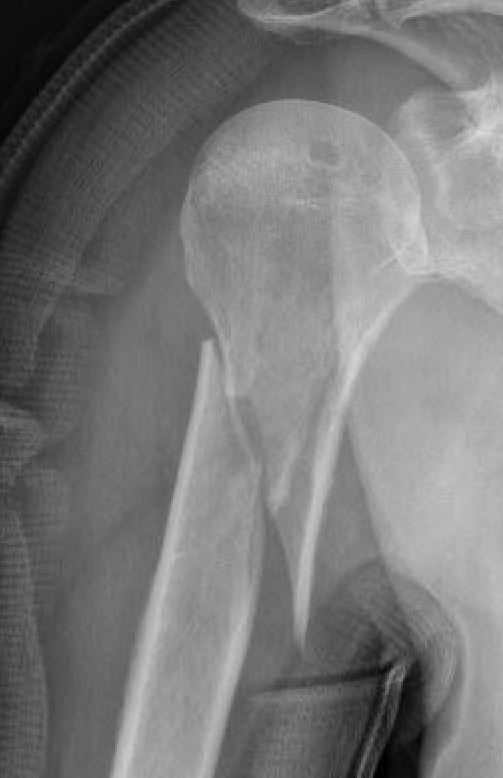

Fracture patterns

- highest risk is transverse fractures

- proximal humerus shaft fractures also at risk due to displacing force of pectoralis and deltoid, and LHB may interpose